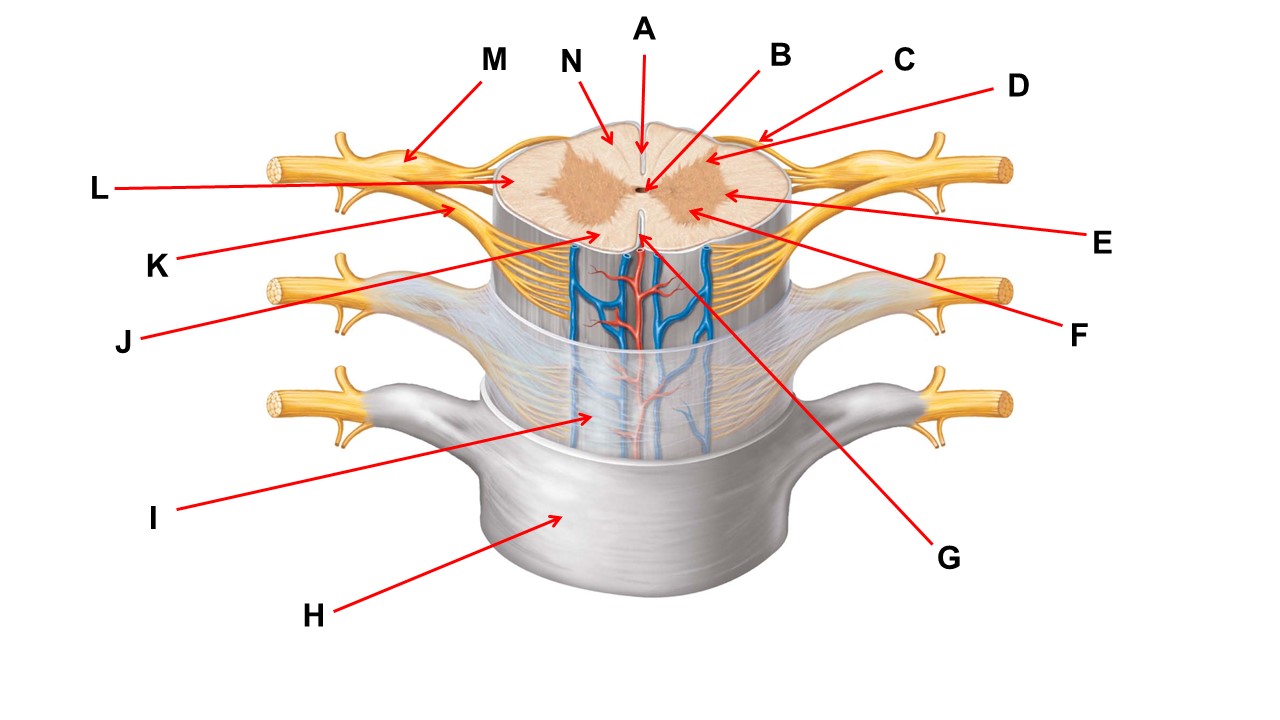

Name the region of tissue surrounding the tip of arrow E.

lateral horn

Name the region of tissue surrounding the tip of arrow B.

dorsal horn

Name the structure at the tip of arrow K.

ventral root

Name the region of tissue surrounding the tip of arrow J.

ventral column

Name the layer at the tip of arrow I.

arachnoid mater

Name the region of tissue surrounding the tip of arrow E.

lateral horn

Name the region of tissue surrounding the tip of arrow N.

dorsal column

Name the deep groove at the tip of arrow G.

anterior median fissure

Which structure(s ) would be found in the area at the tip of arrow D.

cell bodies of interneurons

Name the region of tissue surrounding the tip of arrow E.

ventral horn

Name the region within bracket G.

gray commisure